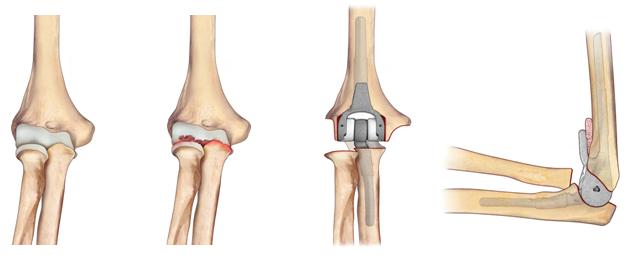

Le situazioni cliniche nelle quali può rendersi necessario un intervento di protesi di gomito sono varie, tutte accomunate dalla presenza di un grave danno della superficie articolare. Tra le malattie degenerative l’artrite reumatoide e l’artrosi, più spesso post-traumatica, sono le indicazioni più frequenti (fig.2). Altre possibili indicazioni sono le fratture recenti dell’omero distale o la pseudoartrosi (mancata consolidazione della frattura) in pazienti anziani con limitate richieste funzionali e con situazioni cliniche tali da rendere impossibile l’osteosintesi.

1) Protesi totale di gomito: riproduce la superficie articolare del gomito mediante due componenti, una omerale e l’altra ulnare (Fig. 3). L’accoppiamento tra le componenti protesiche che scorrono tra loro durante il movimento del gomito è metallo-polietilene. A seconda della presenza o meno di una cerniera -che crea un vincolo meccanico tra la componente omerale ed ulnare- le protesi totali di gomito si dividono in:

- con cerniera (linked): modelli che presentano una stabilità intrinseca e consentono un più ampio spettro di indicazioni (Fig. 3). Attualmente tali modelli sono i più comunemente utilizzati in Italia e Stati Uniti.

- senza cerniera (un-linked): modelli che affidano la stabilità alla ricostruzione capsulo-legamentosa e al buon bilanciamento delle parti molli, impiantabili solo in condizioni con ottima conservazione dell’osso e dei legamenti collaterali.

2) Emiartroprotesi omerale: prevede la sostituzione della sola estremità distale dell’omero con una protesi in metallo che ne riproduce la forma (Fig. 4) e che si deve bene adattare alla superficie ulnare e radiale contrapposta.

Questo impianto di più recente introduzione trova indicazione tipicamente in fratture dell’omero distale pluriframmentarie con impossibilità alla sintesi, in pazienti anziani con discrete richieste funzionali, in cui una protesi totale richiederebbe delle restrizioni maggiori da parte del paziente.